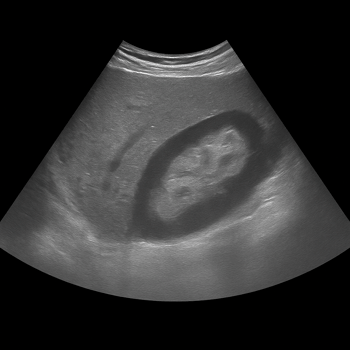

Kidney ultrasound is a quick and gentle examination that can show the kidneys’ size, shape, and any potential changes.

Ultrasound Kidneys

• Ultrasound kidneys show stones, cysts, fluid accumulation and changes in the kidney tissue.

• Used for pain, blood in the urine, swelling or elevated kidney values.

• Quick, painless and radiation-free examination of the kidneys and urinary tract.

• Written report from radiologist and doctor included.